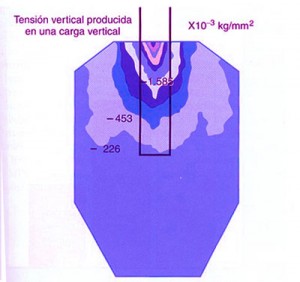

REF: SEGUNDA ENTREGA DEL CURSO: ANATOMÍA OCLUSAL INDIVIDUAL — ABBUTMENTS ANGULADOS POR IMPLANTES INCLINADOS Las piezas dentarias presentan un diseño biomecánico que a partir de su perpendicularidad a la Espiral Dinámica (Willams Mc Horris .Visión tridimensional de la Curva de Spee y de la Curva de Wilson.) reciben las fuerzas de manera axial al hueso receptor. Aplicando técnicas de análisis tridimensionales de elementos finitos y métodos fotoelásticos se ha podido comprobar que cuando se aplican cargas anguladas se producen grandes tensiones a nivel de la cresta ósea.(Misch). (Tomado de Misch) Con una angulación entre 0º y 15 º del abuttment la concentración de tensiones en la zona de la cresta es similar. — ALTURA DE LA CORONA Otro concepto importante es la Relación Corono – Implantaria. Sabemos que debido a la pérdida en altura del hueso es frecuente observar que el largo coronario supera el largo de la implantación endo ósea, situación que es según Misch, mas comprometida en importancia a la de la angulación del abbutmentt , provocando mayores reabsorciones crestales en el caso de recibir fuerzas no axiales. De la misma manera que en la oclusión dentaria, esta situación es manejable en Implantología actuando de manera axial sobre la pieza implantada o dentaria para que las fuerzas recaigan sobre el eje implantario o dentario. En ese sentido es importantísima la situación de los Contactos Interoclusales de manera Tripódica para mantener la Axialidad y sobre todo la Estabilidad de la Oclusión supra Implantes. Misch encuentra útil utilizar coronas de baja Altura Cuspídea incrementando el surco central dos o tres milímetros, con lo cual desde mi punto de vista no solo se disminuye la Eficacia Masticatoria, sino que se acerca al concepto de Céntrica Larga lo que a mi juicio incrementa el juego muscular e induce al Bruxismo.- En cuanto al contorno coronario, debido a que la mayoría de los Implantes tienen una plataforma menor en su emergencia que la que presentan la piezas naturales, es lógico reducir dichos contornos para evitar atrapamiento de alimentos y lograr una correcta fisioterapia natural de la encía peri implantaria. Es por eso la “Premolarización “ un recurso adecuado ya que recordemos que un premolar contiene en su estructura Oclusal la mitad de los componentes anatómicos de un molar los que aún así, cumplen con los conceptos de una OCLUSIÓN ORGANIZADA. REF: SEGUNDA ENTREGA DEL CURSO: ANATOMÍA OCLUSAL INDIVIDUAL Lo importante es que la plataforma del Implante se encuentre debajo de la resultante de las fuerzas axiales. Como dijimos es fundamental relacionar la anchura coronaria con el diámetro de la plataforma del Implante.(Misch). Crestas Estrechas Crestas Estrechas Premolarización Sin embargo si se tiene en consideración el Área Funcional Oclusal (de punto de contacto A a punto de contacto C (45% de su ancho total coronario), observaremos que la reducción coronaria en sentido vestibulo lingual o palatino, no altera la Eficacia Masticatoria ya que las áreas coronarias periféricas a la zona funcional solo sirven para conducir el alimento hacia la inserción del Implante produciendo el masaje fisiológico del alimento , y como la superficie de emergencia es menor que en un diente, lo que se conserva es la parte auténticamente necesaria y funcional de la cara oclusal. Funcionalidad Molar en el Plano Frontal REF: SEGUNDA ENTREGA DEL CURSO: ANATOMÍA OCLUSAL DE CONJUNTO EN EL PLANO FRONTAL Para obtener Axialidad en hueso Div. A es preciso conservar perpendicularidad entre el Implante y la Fosa Central de la Corona, pero a mi juicio, eso solo debe tener una recepción de la carga mediante puntos de contacto equilibrados preferentemente Tripódicos, ya que es el Tripodismo el esquema mecánico básico de estabilidad en la Física Mecánica. En el hueso Div . B –C y D ese eje debe lingualizarse dado el sentido de la reabsorción que se produce. (Tomado de Misch) Oclusion implanto asistida 1ª parteBinderman en un estudio de elementos finitos realizado en la década del 70, concluyó que todos los diseños de Implantes estudiados soportaban menor tensión si la carga era axial al eje mayor del Implante.

A partir de 15º estas tensiones se incrementan en un 50 % o más en la zona vestibular.